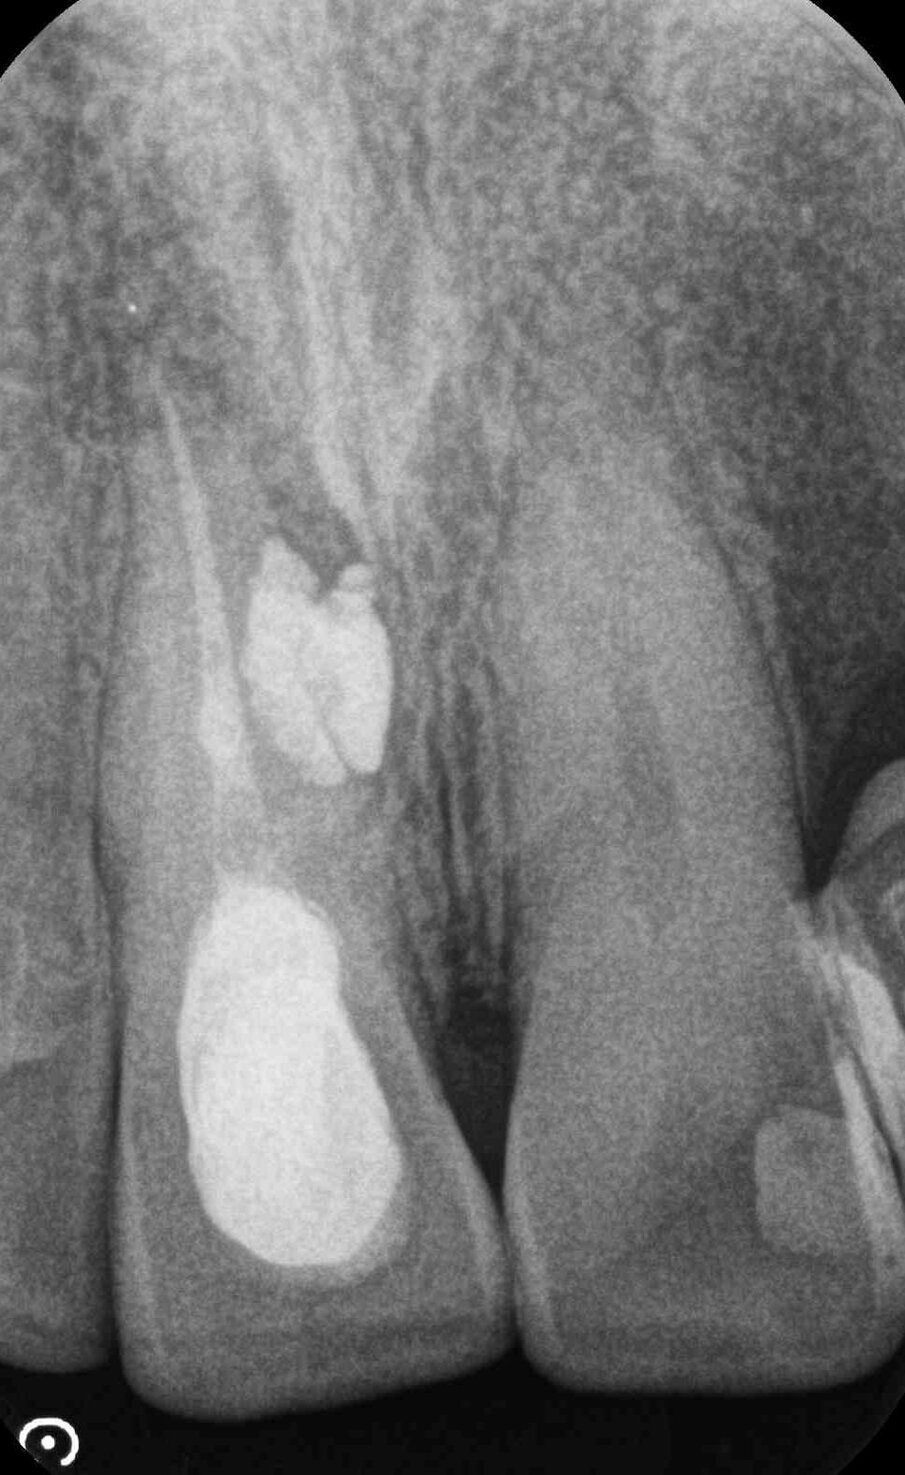

Nei primi mesi del 2016, tuttavia, il paziente perde l’impianto in sede 22, ha fastidio nel settore frontale e nota un “brufolino”, ma per il professionista è tutto a posto. Non convinto, l’insegnante effettua una consulenza da un altro odontoiatra e scopre che il dente 11 ha dei problemi. È compromesso da un processo infettivo cronico (area di rarefazione radiograficamente evidenziabile) con evidenza radiografica e una fistola, prima inesistente. C’è una perforazione iatrogena della radice del dente, con sbuffo di materiale radiopaco nel parodonto.

In parole semplici il paziente scopre che la terapia è stata mal eseguita e ha prodotto un danno (falsa strada). Risulta necessario un secondo intervento ortogrado e retrogrado da parte di uno specialista in endodonzia dal costo di 850 euro. Ai controlli successivi le problematiche rientrano. Il giovane insegnante protesta con il primo odontoiatra, chiede indietro quanto ha speso per il trattamento del dente 11 (ossia 250 euro) e per l’intervento endodontico di recupero del dente, 850 euro, per un totale di 1.100 euro.